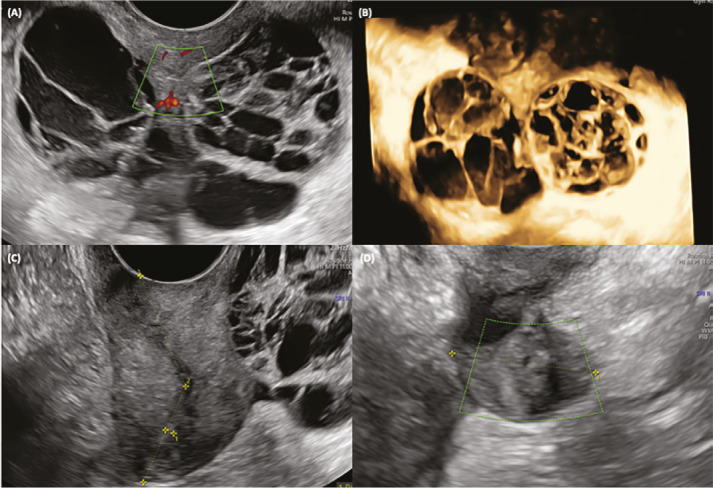

Abstract Image